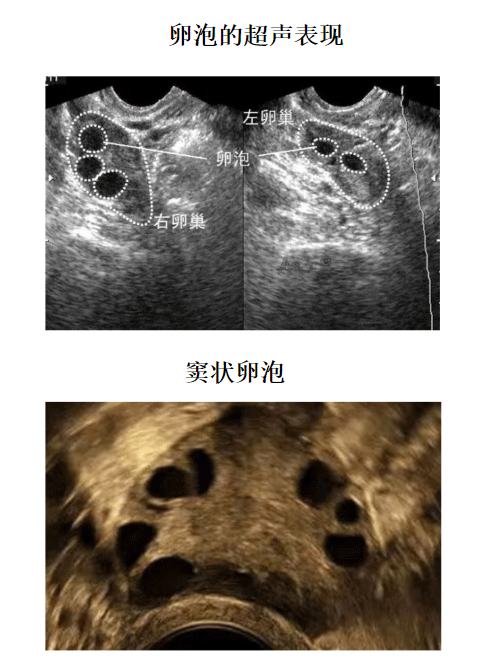

2、多囊卵巢综合征引起的女性不孕,多囊卵巢综合征是引起女性排卵障碍的常见疾病,通过卵泡监测能够发现有很多细小的卵泡,但是不能发育成熟达到排卵要求。

卵泡监测方法就是阴道B超检测,如果想要更加准确的判断卵泡发育程度、排卵日和黄体功能如何的话,建议配合基础体温检查,每次检查时间很短,不用担心花费太多时间。

试管婴儿卵泡监测流程从促排卵后的第5天开始,监测卵泡生长状况,这个时候可以两天监测一次、三天监测一次,一些患者需要抽血检查雌激素,当在促排卵第9天的时候,就需要每天监测一次,直到卵泡成熟,注射夜针(HCG)后,就可不用监测了。

A:如果卵泡监测到卵泡大小在12mm以下的时候,三天一次,当监测到卵泡大小为12mm以上的时候,建议一天监测一次,当卵泡趋近成熟的时候,可能需要一天监测两次,如果一直没有监测到卵泡,也是三天一次,后面根据卵泡数量进行跟进,一直监测到卵泡成熟为止。